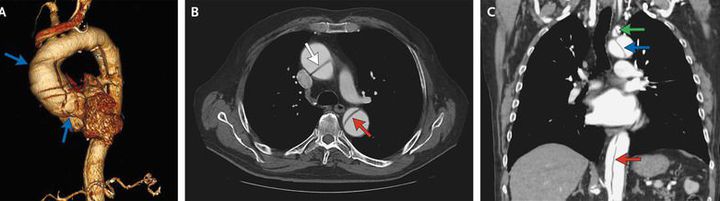

An 81-year-old man with no documented medical history presented to the emergency department with suprapubic pain and urinary retention resulting from benign prostatic hyperplasia. He was incidentally found to have an elevated troponin I level, at 0.17 ng per milliliter (normal value, <0.08). He reported no chest or back pain or shortness of breath. There was no evidence of ischemic changes on electrocardiography. Chest radiography showed widening of the mediastinum. Transthoracic echocardiography showed aneurysmal dilatation and a dissection flap in the ascending aorta (video). Computed tomographic angiography of the thorax and abdomen revealed an ascending aortic aneurysm (Panel A, blue arrows) and a type I DeBakey aortic dissection. The dissection involved the ascending aorta (Panel B, white arrow), aortic arch (Panel C, blue arrow), and descending aorta (Panels B and C, red arrows), terminating just below the origin of the renal arteries. Several branch vessels were involved as well, including the right brachiocephalic artery, left subclavian artery (Panel C, green arrow), and superior mesenteric artery. Given the absence of associated symptoms, the dissection was thought to be chronic. The patient declined consideration of surgical intervention but agreed to treatment with a beta-blocker. One year later, the patient's condition had not worsened; he continued to be treated with a beta-blocker and to receive routine follow-up care.